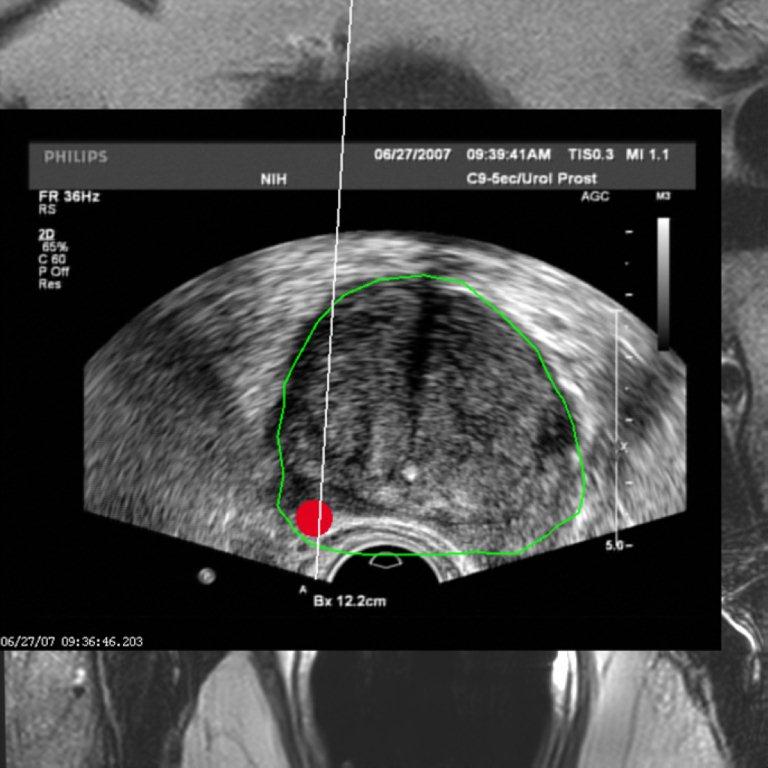

Die permanente Brachytherapie (brachy = kurz, also „Kurzdistanzbestrahlung“) oder Seedimplantation ist eine kurative (heilende) und gleichzeitig besonders schonende Form der Strahlentherapie beim lokal begrenzten Prostatakarzinom. Aufgrund ihrer hohen Wirksamkeit wird sie immer häufiger als Alternative zur radikalen Prostatektomie, der Totaloperation, eingesetzt. Mit Hilfe spezieller Hohlnadeln werden die Strahlenquellen in Form von winzigen radioaktiven Implantaten (Seeds) bei diesem Verfahren direkt in die Prostata eingebracht. Als radioaktive Quellen werden Iod (I-125) oder Palladium (Pd-103) eingesetzt. Auf diese Weise können deutlich höhere Strahlendosen direkt in der Prostata mit Schonung umliegender Organe verabreicht werden als bei einer externen Bestrahlung. Die Implantate verbleiben in der Prostata und geben die Strahlung langsam abnehmend über mehrere Monate (bei Iod-125 in etwa 12 Monaten und bei Palladium-103 in etwa 3 Monaten) unmittelbar in das Tumorgewebe ab. So wird das Prostatakarzinom allmählich zerstört, ohne dass gesundes Gewebe wesentlichen Schaden erleidet.